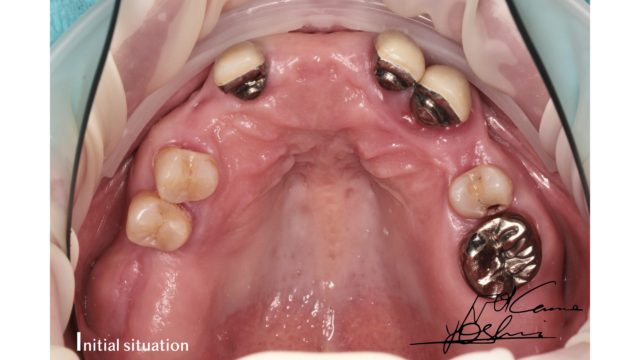

お口の上部、BEFORE写真です。